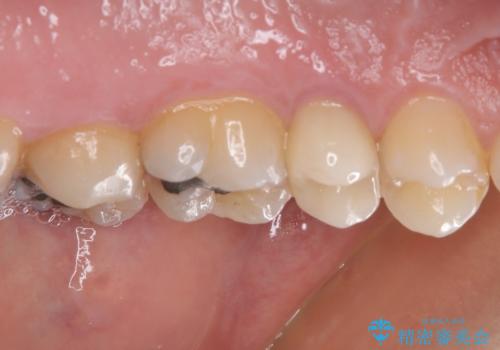

インプラント処置は、抜歯即時埋入を行い、十分な安定性が確認できたため、当日仮歯を装着しました。

インプラントが生着するのを待っている間に反対側の根管治療を行い、左右同時に補綴治療を行いました。

補綴治療後3ヶ月での経過は良好で、引き続き経過観察を行っていきます。